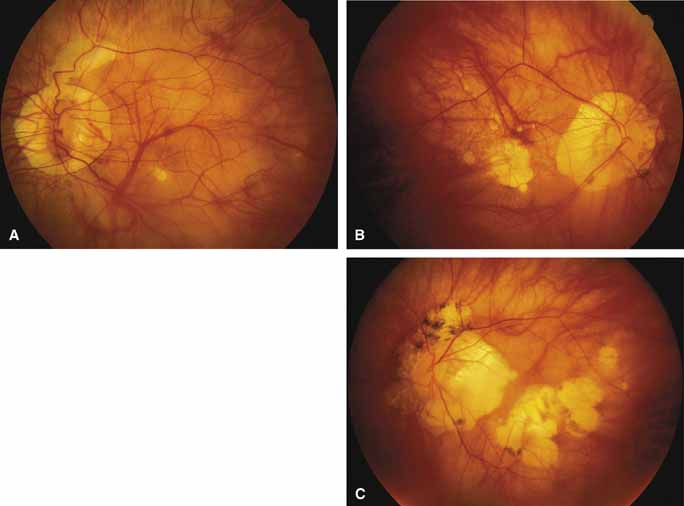

First described by Nettleship12 in 1884, central areolar choroidal dystrophy (CACD) (MIM No. 215500, Phenotype catalog number (MIM) from McKusick VA: Mendelian Inheritance in Man. Catalogs of Human Genes and Genetic Disorders. 12th ed. Baltimore: Johns Hopkins University Press, 1998 [http://www.ncbi.nlm.nih.gov/Omim/]), as it is most appropriately called,13 has been described under many names, including central areolar choroidal sclerosis, central areolar choroidal atrophy, central angiosclerosis, and central senile choroiditis.14,15 The disorder can be autosomal dominant or autosomal recessive, and phenocopies can occur from many other diseases, including mutations of peripherin/RDS16–19 and advanced stages of macular dystrophies (see later text). A locus for CACD has been identified on chromosome 17p.20 The earliest symptoms result from pericentral scotomas and include difficulty reading, poor dark adaptation, reduced visual acuity, and glare sensitivity. The earliest fundus findings are subtle and include pigment epithelial and choriocapillaris lesions in the macula (Fig. 1A) that enlarge and eventually form the punched-out central atrophic lesions typical of this disease (Fig. 1B). Histopathology shows fibrotic scarring with absence of choriocapillaris, retinal pigment epithelium, and overlying photoreceptors in the affected areas.21 The Ganzfeld electroretinogram is usually normal early in the course but may become mildly to moderately abnormal for cone and rod responses late in the course of disease when extensive atrophy of the choroid and secondarily the pigment epithelium and neurosensory retina occurs. Recent studies using the multifocal ERG have indicated that the abnormality of retinal function extends beyond the borders of the visible atrophy and is consistent with presynaptic photoreceptor dysfunction.22 The EOG can be normal or mildly abnormal depending on the extent of associated retinal pigment epithelial dysfunction.

Other forms of central choroidal dystrophy exist that do not show the discrete oval lesions of typical central areolar choroidal sclerosis. These forms of central choroidal choriocapillaris atrophy often present with progressive pigment epithelial mottling and patchy choriocapillaris atrophy initially limited to the macula (Figs. 2A and 2B). With time, the atrophy enlarges and eventually encompasses the entire posterior pole (Fig. 2C). For this form of central choroidal atrophy, a gradual transition usually occurs from atrophic central pigment epithelium and choriocapillaris to essentially normal retina and choroid in the peripheral fundus.

Serpiginous choroidopathy, also called serpiginous choroiditis, is a recurrent, progressive, destructive chronic degeneration of the choroid and retinal pigment epithelium that begins around the optic nerve and extends through the posterior pole.44 Unfortunately, some cases of this disorder have been reported under the name geographic helicoid peripapillary choroidopathy, and this has led to confusion with the clearly dominantly inherited genetic disorder first described in Iceland by Sveinsson26 in 1939 as choroiditis areata and subsequently renamed helicoidal peripapillary chorioretinal degeneration.27,28 The etiology of serpiginous choroidopathy is unknown, but the disease is not thought to be genetic. The disease starts as a gray, cream, or greenish discoloration and edema of the retinal pigment epithelium, followed by extension of the lesion, usually away from the disc, in a stepwise fashion (Figs. 8A and 8B). Vitritis is present in one-third of cases. Periods of quiescence or activity can be separated by months to years. Subretinal fibrous scarring, atrophy of the choroid, and hyperpigmentation in adjacent tissues can be prominent features (Figs. 8C and 8D). The prognosis for retention of central vision is poor because the disease process will often involve the macula. Systemic immunosuppression may be effective in prolonging remission and improving the visual outcome.45